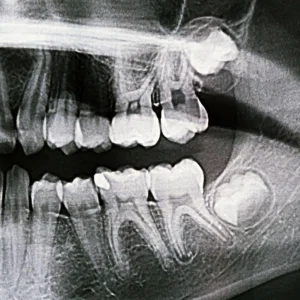

Wisdom teeth removal is a routine dental procedure, yet the recovery process plays a vital role in how quickly and comfortably patients heal. Proper aftercare not only eases discomfort but also helps prevent complications such as infection or delayed healing. If you’ve recently undergone wisdom teeth removal, knowing how to care for your mouth during the recovery period can make the experience far more manageable and reassuring.

Following wisdom teeth removal in Brentwood, it is normal to experience swelling, mild bleeding, jaw stiffness, and tenderness. These symptoms are typically most noticeable within the first two to three days and gradually improve afterward. While many patients return to daily routines fairly quickly, the extraction sites may take up to two weeks to heal fully. Understanding that these effects are part of the normal healing process can help reduce anxiety during recovery.